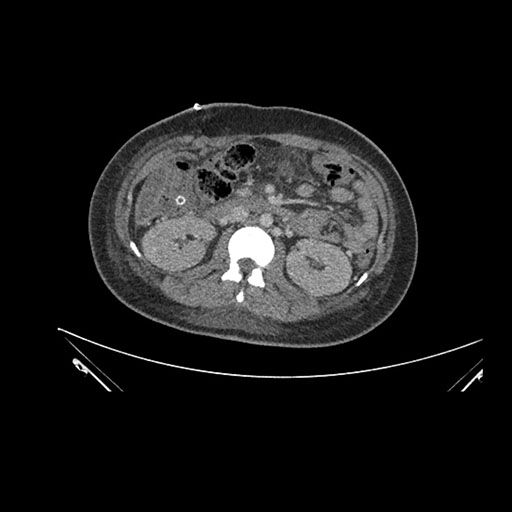

Imaging Analysis

Look through the patient's CT scan to identify any areas of concern for the necessary procedure.

Axial Venous

Based on initial findings, which issue(s) would you be most concerned about?